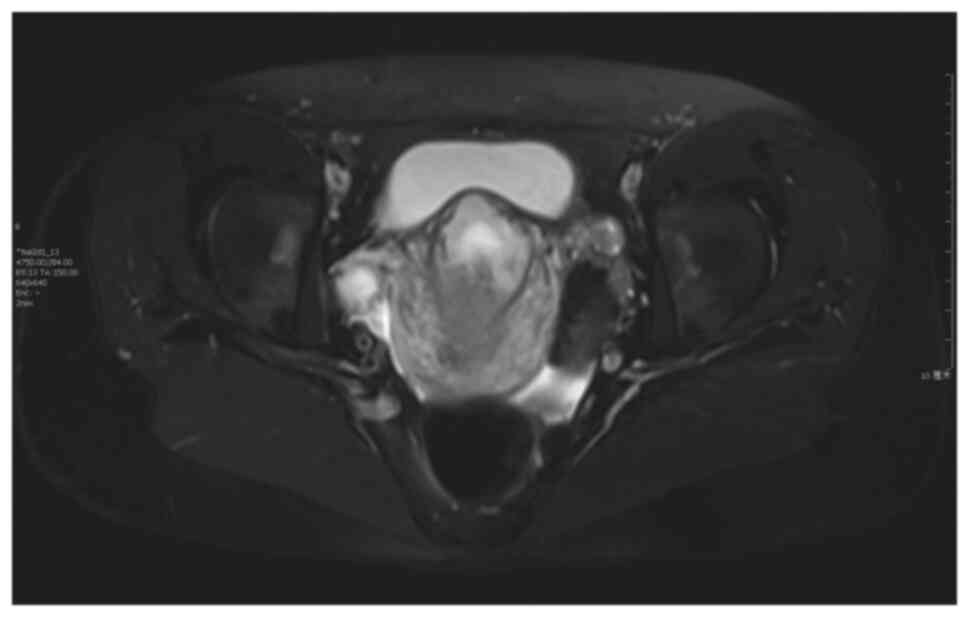

The surgical procedure was as follows: Laparoscopy was performed under general anesthesia in the supine lithotomy position. Laparoscopy displayed a bulging in the lower uterine segment (Fig. 1). Subsequently, a 12 IU vasopressin solution was injected into the uterus. The bladder peritoneum was incised to expose the pregnancy scar; a bulging was noted comprised of blood vessels and gestational tissues. The gestational tissue was rapidly removed with grasping forceps, scissors and an aspirator (Figs. 2 and 3). This procedure was performed as quickly as possible. The myometrial scar was resected and stanched by bipolar coagulation. Finaly, a continuous suture with an absorbable suture (1-0) was used to close the uterine wound (Fig. 4).

Figure 1

Image illustrating a bulging in the lower uterine segment following laparoscopy and the positioning of the gestational sac convex to the bladder (patient 5).

The imaging criteria for diagnosis (Figs. 5 and 6; patient 5) include the following: An empty uterus and cervical canal; the development of the GS toward the anterior wall of the isthmic portion; the loss of myometrial anterior wall continuity on a sagittal plane of the uterus through the GS; the absence of or diminished healthy myometrium between the bladder and the sac; the monitoring of peri-trophoblastic vascular flow with high velocity and low impedance surrounded by the sac using Doppler examination (10,11). The pathological features included trophoblast invasion and destructive growth to the uterine wall. Since the opened blood vessels do not possess systolic function and the scar tissue cannot contract, a potential misdiagnosis leading to an artificial or spontaneous abortion will result in massive hemorrhage (12).

Figure 5

Magnetic resonance imaging of the empty uterus, the empty cervical canal, and the cesarean scar pregnancy (patient 5).

Figure 6

Magnetic resonance imaging of the GS surrounded by the myometrium and absence of the myometrium between the GS and the bladder. GS, gestational sac (patient 5).